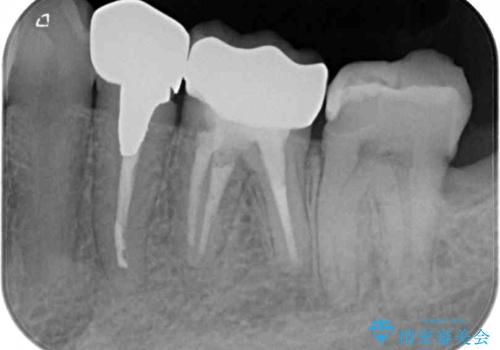

- 下顎左右の奥歯を治療途中で放置してしまっているとのことで来院された患者様です。

欠損部はインプラントによる補綴治療を、土台の外れてしまった歯は、根管治療を行った上で、補綴治療を行うこととしました。